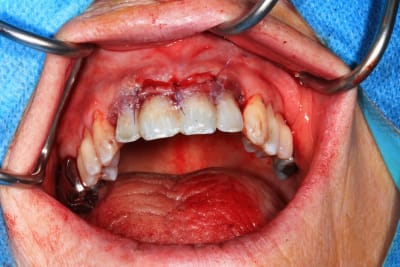

Chir le vendredi matin. au vu de la possibilité de reculer pas mal les implants postérieurs, je trouvais qu'il y avait trop de porté entre les implants : je pars donc sur 6 implants.

Mais malgré les gros renforts, le guide résine n'est pas assez rigide : impossible de poser le bridge en immédiat. obligé de fraiser le bridge ( j'aurais du en prévoir un autre évidé, ce que je prévois pour lundi prochain ) et de mettre des piliers provisoires : 40 m de travail de labo en plus..

Mais un chouette résultat.

Etre capable de tout gerer m'a éviter d'annuler la chir prévu, mais la morale de l'histoire est quand meme de mieux anticiper :)